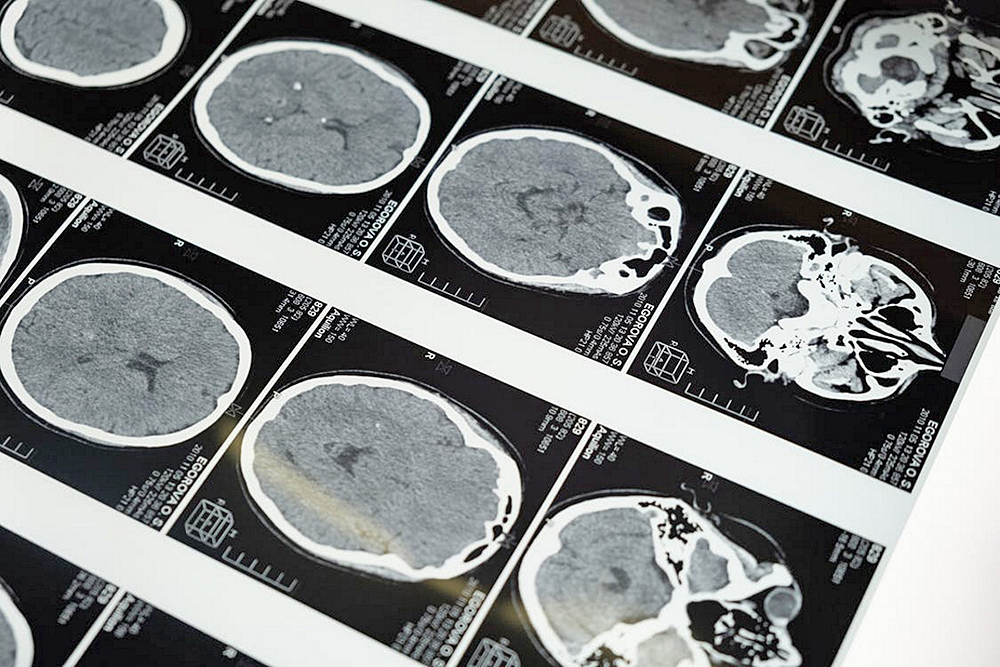

Además, los pacientes podrán someterse a más pruebas resultado de los avances científicos en neurología, tales como una tomografía computarizada (TC) o una resonancia magnética. Asimismo, se pueden hacer tomografías por emisión de positrones (PET) u otros escáneres cerebrales. Sin embargo, solamente se podrá confirmar el diagnóstico con una biopsia.